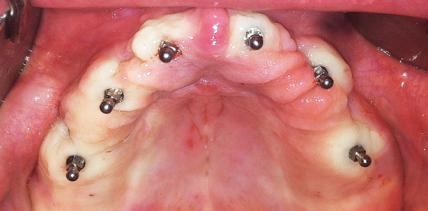

Mini-Implantate: Eine adäquate Therapieoption für Senioren

Jahr 2014, Ausgabe 01, Seite 28 Autoren: Dr. Dr. Eberhard Bender